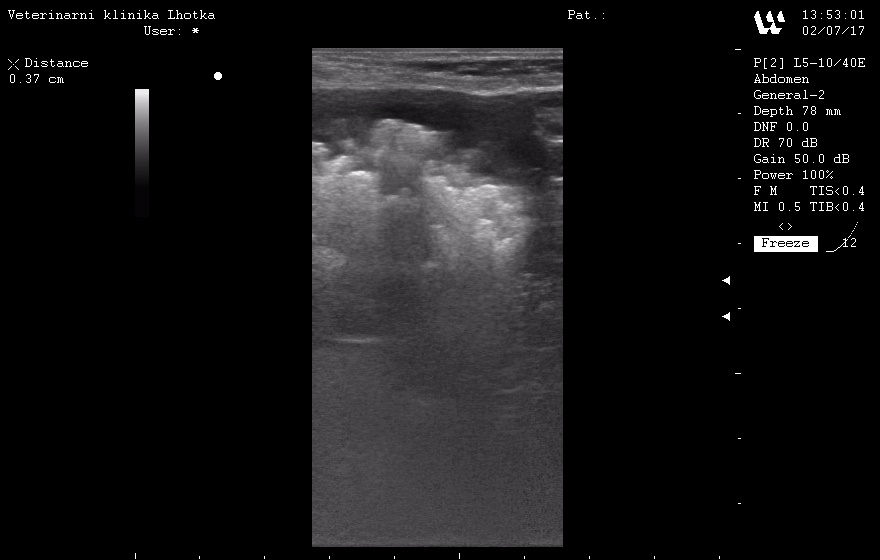

Agáthu jsme klinicky vyšetřili a nenašli žádné abnormality celkového zdravotního stavu. Horší byly ovšem nálezy při sonografickém vyšetření močového měchýře a vyšetření čerstvého vzorku moči.

Při sonografickém vyšetření byl sice močový měchýř jen málo naplněný močí, zato byl plný drobných urolitů  od 2 do 7 mm.

SONO MM před operací 2.jpgSONO MM před operací 1.jpg